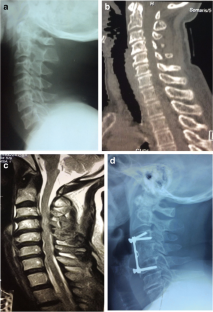

Fig. 2

Patients with cervical spine injury (413) were retrospectively reviewed. Six patients with neurological deficits were identified to have disc herniation without adjacent bone lesion. The diagnosis was confirmed by MRI. The Japanese Orthopedic Association (JOA) score was used to assess the severity of clinical symptoms. Different grading systems have been used in analyzing various stages of herniated cervical discs. All patients underwent anterior cervical decompression, insertion of autologous iliac crest graft, and fixation with cervical plate.

The causes of injury were road traffic accidents in four patients and sport and domestic accidents in one patient each. There were five patients with single intervertebral disc herniation and one patient with double. Pre-operative JOA score was 14 for three patients, the remaining three patients scored 10, 6, and 3 respectively. At final follow-up, the score was 17 for four patients and 14 for two patients.

Traumatic cervical disc herniation with neurologic deficit and without adjacent bone lesion is a rare condition. MRI is the golden examination to confirm diagnosis. Early recognition is essential for appropriate therapy and to minimize the extent of neurological deficit.

The MRI is mandatory in diagnosing different types of traumatic herniated cervical disc. Discectomy and anterior cervical interbody fusion using autologous iliac crest graft are the treatment options.